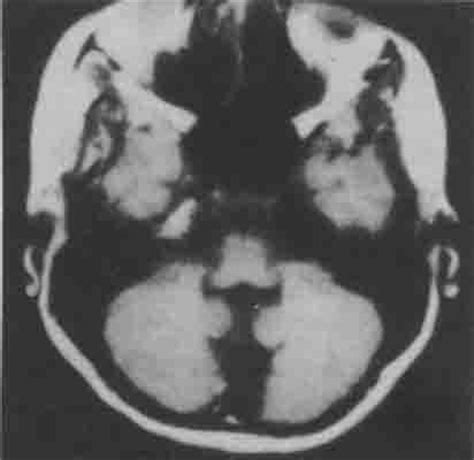

4.颅脑CT主要用于明确有无器质性病变及病变部位等。常见的异常包括广泛性脑瘫、脑软化及白质发育不良等。对于部分病例可用于提示病因,如先天性脑发育畸形、宫内感染等。

新生儿脑发育不良的诊断方法是什么?由于婴幼儿期的精神和身体发育速度存在着个体差异,故除参考正常儿童发育标准外,还需结合详细的养育史和家庭环境,社会环境等因素,进行综合判断。那么,新生儿脑发育不良的诊断方法是什么?以下就是我们的权威专家针对脑发育不良的诊断方法给大家进行详细介绍。 新生儿脑发育不良的诊断方法是什么? 1、CT、MRI扫描:根据病变处密度增高这一现象,CT、MRI扫描可扫描出各层次具体的内部结构和脑组织的不同图像,进而进行诊断有无脑发育不全。 2、X射线头颅平片:为脑发育不全的诊断提供颅压增高及定位的证据。 3、超声波诊断:中线波向健侧移位。通过观察B超断层现象判断占位病变位置的大小,这也是脑发育不全的先进诊断方法。 4、放射性同位素脑扫描,可见同位素浓集现象。 5、检查有无浅表淋巴结肿大,并结合病史,进行具体神经系统诊断。》》》想要了解更多关于治疗脑发育不良疾病的知识, 点击此处咨询相关专家》》》 目前治疗脑发育不全最好的方法就是神经组织修复疗法: 神经组织修复疗法,就是从神经系统疾病的根源入手,通过患者自身修复对神经系统具有重要再生促进作用的神经细胞,通过靶向定位、微创介入或穿刺的方式,注入患者体内。神经细胞通过血液循环穿过血-脑屏障,促进神经元和神经胶质细胞的再生,促进受损神经细胞的修复,产生神经营养物质供给体内神经细胞,健康的神经细胞修复、替代受损、凋亡的神经细胞,逐渐恢复患者神经系统的正常功能。 新生儿脑发育不良的诊断方法是什么?以上就是关于脑发育不良的诊断方法给大家的详细介绍了,相信大家对此已经有所了解了,希望能够给您带来帮助。神经组织修复疗法是治疗脑发育不良最好的方法,希望给患者带来帮助。如果您还有哪些地方不明白,可以咨询我们的在线专家,我们将竭诚为您服务。 推荐相关阅读:脑发育不良治疗效果好的医院脑发育不良治疗的医院哪家好儿童脑发育不良怎么治疗好?小儿大脑发育不良要怎么治疗?治疗脑发育不良最好的医院在哪

我看了你孩子的MRI,是个小脑发育不良,主要是影响平衡功能,所以孩子不会走,应该进行康复治疗,小脑发育不全一般不影响智力。